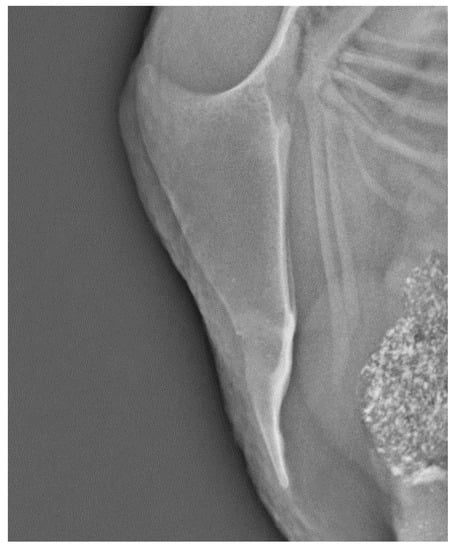

- Baur, S.; Rufener, C.; Toscano, M.J.; Geissbühler, U. Radiographic evaluation of keel bone damage in laying hens—morphologic and temporal observations in a longitudinal study. Front. Vet. Sci. 2020, 7, 7. [Google Scholar] [CrossRef] [PubMed]

- Rufener, C.; Baur, S.; Stratmann, A.; Toscano, M.J. A reliable method to assess keel bone fractures in laying hens from radiographs using a tagged visual analogue scale. Front. Vet. Sci. 2018, 5, 124. [Google Scholar] [CrossRef]